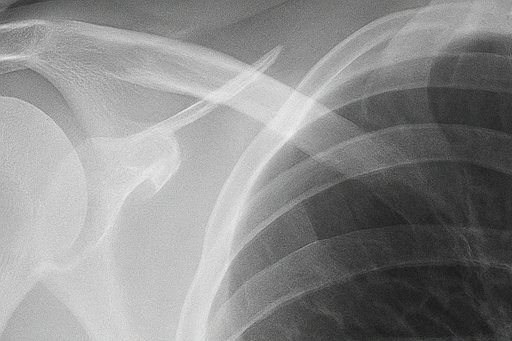

(2) 흉부 X선 검사

흉부 X선 촬영은 가장 기본적이고 신속한 진단 방법입니다. X선 영상에서 공기가 찬 부위는 검게 보이며, 허탈된 폐는 중심 쪽으로 쪼그라든 형태로 나타납니다. 이를 통해 폐 허탈의 범위와 기흉의 크기를 확인할 수 있습니다. 그러나 폐 상부의 작은 공기집(bleb)은 X선으로 잘 보이지 않아, 필요한 경우 흉부 CT 검사를 시행합니다.